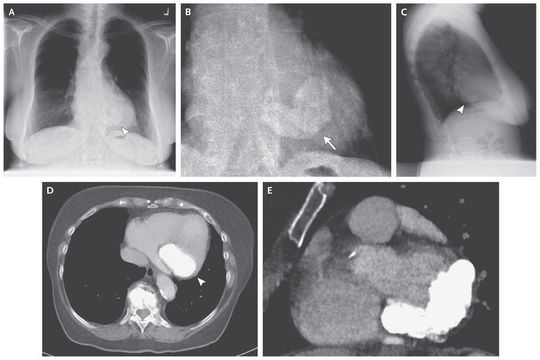

An 81-year-old woman was transferred to the medical service with cardiac failure after surgery for oral cancer. A diagnostic workup indicated perioperative overhydration and pulmonary embolism as causative factors for her symptoms. Chest radiography revealed a large, dense area of calcification overlying the heart, consistent with mitral annular calcification. Calcification was semicircular in the location of the mitral valve, as seen on the preoperative posterior–anterior view (Panel A, arrowhead; Panel B, arrow, shows an enlarged view) and a lateral view (Panel C, arrowhead). Computed tomography revealed calcification of the posterolateral mitral-valve annulus on the axial view (Panel D, arrowhead) and the short-axis view (Panel E). Transthoracic echocardiography revealed moderate mitral regurgitation and stenosis, left ventricular diastolic dysfunction, and a left ventricular ejection fraction of 69%. Mitral annular calcification is often detected on routine chest radiographs in elderly patients and is considered to be a degenerative condition that is usually unrelated to clinical symptoms. When mitral annular calcification is massive, it can lead to valvular dysfunction (as in this patient), typically resulting in complete heart block, mitral regurgitation, or less often, mitral stenosis. Mitral annular calcification may be related to diabetes, hypertension, hyperlipidemia, and secondary hyperparathyroidism from renal failure. During her hospitalization, the patient was conservatively treated with oral heart medication. No surgery was performed, and the patient was lost to follow-up.